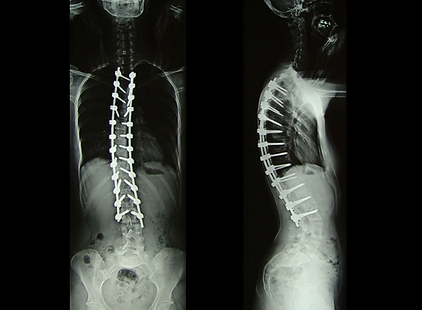

Scoliosis is a spinal deformity characterized by lateral deviation of the vertebrae and which can progress rapidly in childhood and in the early adolescence.

In these cases, surgical correction can be required.